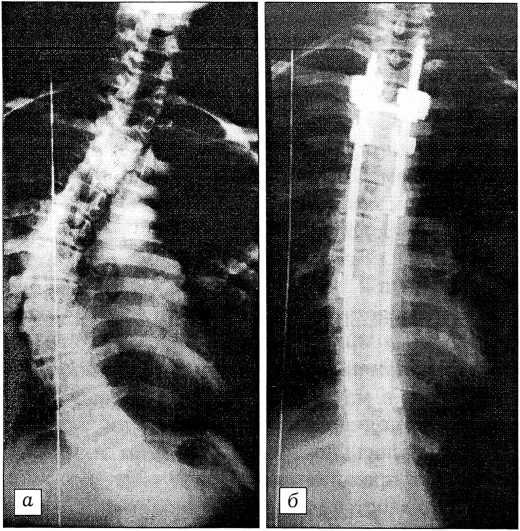

Средняя величина первичной сколиотической дуги равнялась перед операцией 60,1° (38- 94°), после операции 29,2° (15-57°). Таким образом, средняя коррекция составила 30,9°, или 50,8% (39,4-65,6%) (рис. 1).

Рис. 1. Больная Л. 16 лет. а — до операции: правосторонняя грудная деформация 64°; б — после операции: величина дуги 25° (через 6 мес потери коррекции нет).